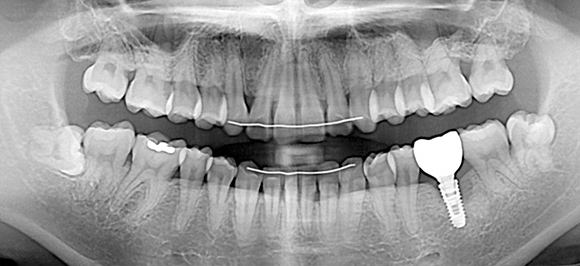

임플란트 재수술

상악동과 더불어 치과치료 중 난이도가 높은 임플란트

기존 임플란트가 빠지거나 흔들린다면 이를 제거하고 인공치근을 재식립

재수술이기 때문에 악화된 상태에 따라 그만큼 견고한 치료가 요구